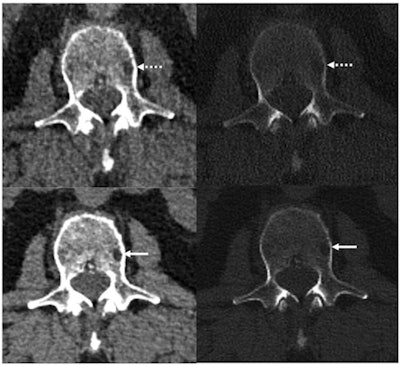

Reference protocol (top) and evaluated protocol (bottom) images in a 74-year-old man with multiple myeloma. Soft-tissue reconstruction is shown (left side; window width, 400; window level, 40), whereas the right column is the bone reconstruction (right side; window width, 3700; window level, 600). A lytic bone lesion in the L3 vertebral body is more conspicuous on the noncontrast-enhanced axial photon-counting CT reconstruction images (bottom; solid arrows) compared with the noncontrast-enhanced axial energy-integrating detector CT reconstruction images (top; dashed arrows). Image and caption courtesy of the RSNA.Whole-body low-dose CT has a mean effective dose that ranges between 4 mSv and 8 mSv, but low-dose images can be noisy. Photon-counting CT shows promise for imaging bone disease caused by multiple myeloma because its smaller detector pixel sizes eliminate the need for the high-spatial-resolution filters that conventional CT requires -- which translates not only to better dose efficiency but also less noise.

The investigators found that photon-counting CT had 23% lower image noise compared with conventional CT imaging at the same radiation dose. Assessment of the 2-mm images showed that photon-counting CT enabled visualization of particular bone disease features such as lytic lesions, intramedullary lesions, fatty metamorphosis, and pathologic fractures better than did conventional CT (p = 0.05); the 0.6-mm photon-counting CT images with neural network denoising produced these same results and enabled visualization of more lytic lesions compared with conventional CT in 21 of 27 patients.